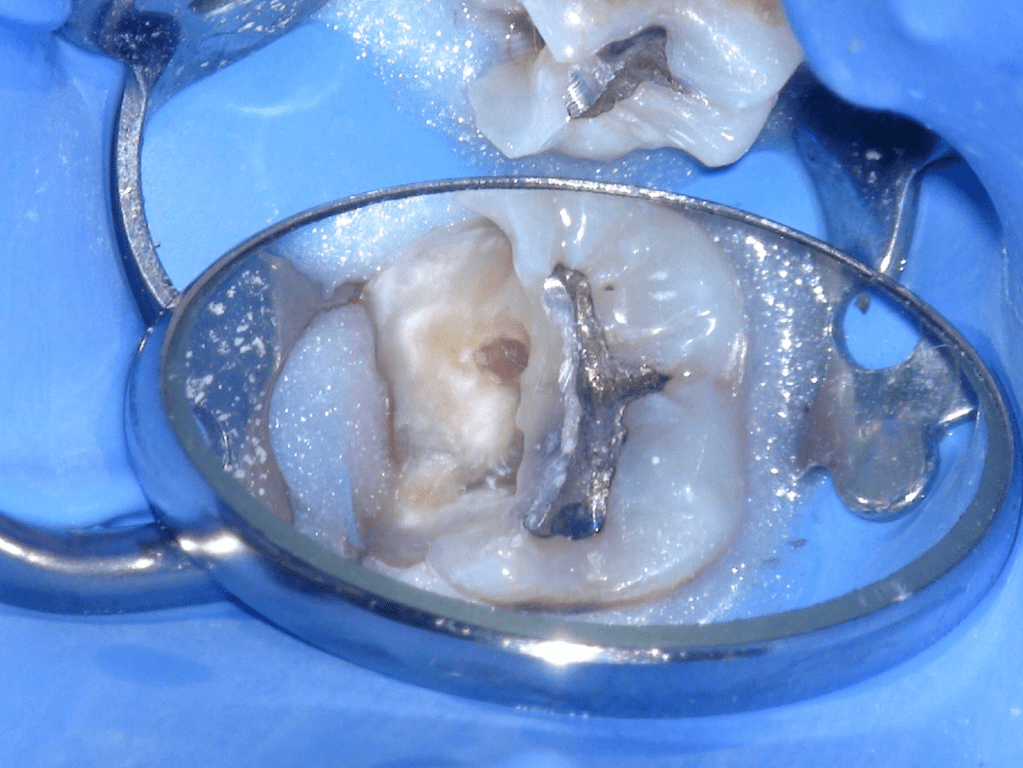

Fisura, remoción amalgama para explorar